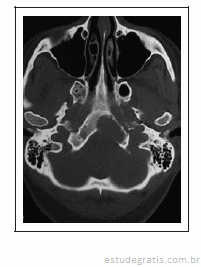

Uma mulher de 44 anos de idade passou a apresentar, na última semana, episódios esporádicos de parestesias em hemiface esquerda. Por duas vezes, apresentou dificuldade para ingerir líquidos. Apresentou três episódios de vertigens rotatórias e vômitos. De patologias pregressas, apenas hipertensão arterial leve, controlada com uso de losartana. O exame neurológico é normal. Não há alterações objetivas no exame nos nervos cranianos. Hemograma, glicemia, dosagem de derivados nitrogenados, eletrólitos no sangue: tudo normal. Exame de neuroimagem, reproduzido a seguir, mostra a presença de uma lesão expansiva osteolítica no terço inferior do clivus, à esquerda, que se estende até o arco anterior do atlas.